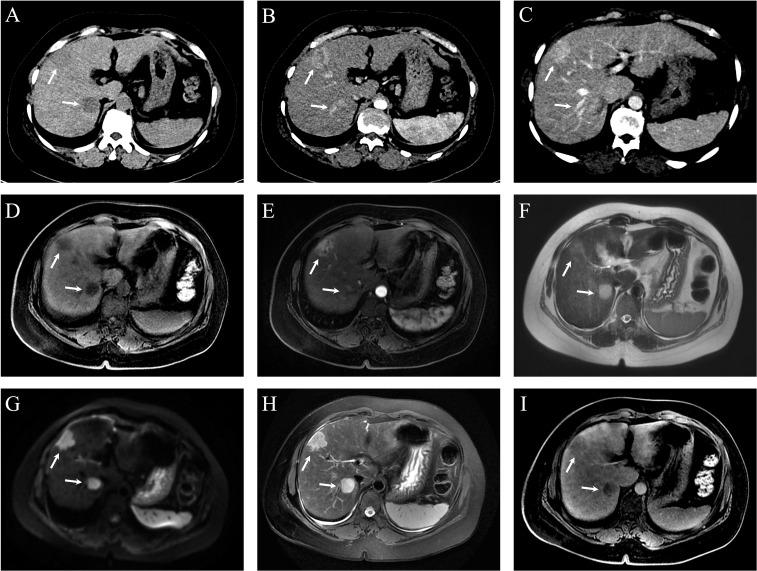

Simultaneous occurrence of primary hepatocellular carcinoma (HCC) and intrahepatic cholangiocarcinoma (ICC) is rare. We report two cases of synchronous double primary HCC and ICC (sdpHCC-ICC), both associated with chronic hepatitis B. Case 1 involves a 63-year-old man whose liver lesions were incidentally found during routine screening. Preoperative imaging revealed lesions in the S4 and S5 liver segments, with postoperative confirmation of sdpHCC-ICC. He received hepatic arterial infusion chemotherapy (HAIC) and transcatheter arterial chemoembolization (TACE) combined with gemcitabine and oral S-1 over 26 months, with no recurrence observed. Case 2 describes a 48-year-old woman presenting with right upper abdominal pain. Preoperative imaging identified a lesion at the S6/7 and S8 junction, later confirmed as sdpHCC-ICC. Postoperative TACE was performed at 1.5 and 3 months, and lenvatinib was introduced at 3.5 months. She remained recurrence-free at the 21-month follow-up. While the precise pathogenesis of sdpHCC-ICC remains unclear, chronic HBV infection plays a pivotal role. Surgical resection remains the primary treatment, though prognosis is generally poor due to the ICC component.

原发性肝细胞癌(HCC)和肝内胆管癌(ICC)同时发生的情况较为罕见。我们报告了两例同步性双原发性HCC和ICC(sdpHCC-ICC)病例,两例均与慢性乙型肝炎相关。病例1为一名63岁男性,其肝脏病变在常规筛查中偶然发现。术前影像学检查显示肝脏S4和S5段有病变,术后确诊为sdpHCC-ICC。他接受了26个月的肝动脉灌注化疗(HAIC)以及经动脉化疗栓塞(TACE)联合吉西他滨和口服S-1治疗,未观察到复发。病例2描述了一名48岁女性,表现为右上腹疼痛。术前影像学检查在S6/7和S8交界处发现一个病变,后来确诊为sdpHCC-ICC。术后分别在1.5个月和3个月进行了TACE,并在3.5个月开始使用仑伐替尼。在21个月的随访中她未出现复发。虽然sdpHCC-ICC的确切发病机制尚不清楚,但慢性HBV感染起着关键作用。手术切除仍然是主要治疗方法,不过由于存在ICC成分,总体预后通常较差。